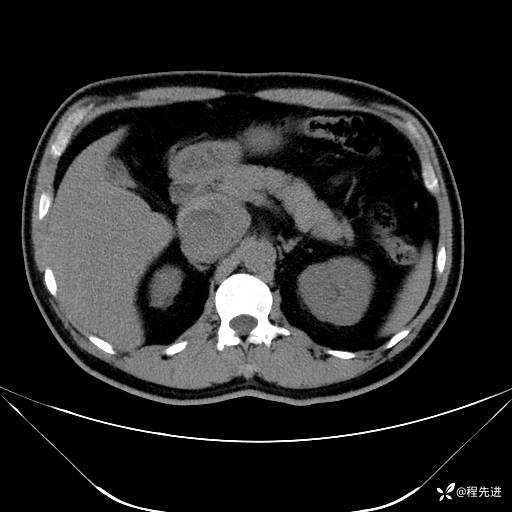

【腹盆】特别精彩病例|发现腹膜后肿物1月余

患者性别:男

患者年龄:42岁

主诉:发现腹膜后肿物1月余

现病史:患者1月余前查体,行超声检查提示:后腹膜囊实性肿块;慢性胆囊炎伴胆囊内结石;无腹痛腹胀,不伴腹泻发热等;偶感腰背部酸痛。

CT平扫+增强: